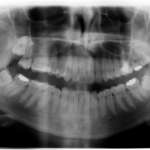

Come si valuta la difficoltà dell’intervento di estrazione dei terzi molari? ... Premium

Stabilire il grado di complessità di un’estrazione dei terzi molari è fondamentale sia per il chirurgo che per il paziente. Gli aspetti clinico-radiografici forniscono...